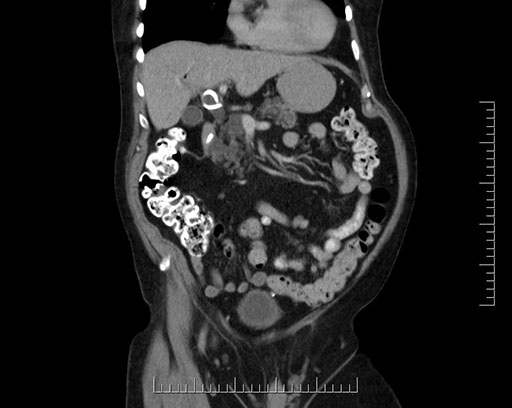

Coronal - stented